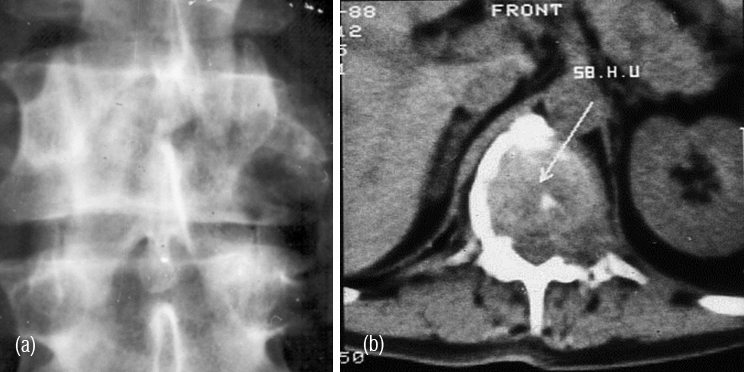

It is a solitary lesion and can be encountered in any bone. However, it is common in the spine. Most of the benign looking plasmacytomas when followed may develop into multiple myeloma eventually. Radiologically, a plasmacytoma is an expanding lytic lesion without any calcification or new bone formation. When it involves the vertebral body a compression fracture may be seen. When marked compression is seen vertebral plana is noted (Figure 1abc). To differentiate from metastasis, it is stated that in metastasis pedicles are involved earlier as they are vascular (2ab). However, when a large part of the body is involved in myeloma, pedicles also may be destroyed (Figure 3abc).

CT and MRI demonstrate lytic areas with struts of bone interspersed. In MRI, plasmacytoma shows a classical minibrain appearance (Figure 4abc). At times, it is difficult to differentiate hemangioma from plasmacytoma (Figure 5ab). It may remain localized for many years but more than 30% progress quite rapidly to generalized myelomatosis with a latent interval of 5-10 years. Radiological features are listed in table 1.

Figure 2: (a) Plasmacytoma of L2, (b) CT guided biopsy.

Figure 5: (a) CT (post op.), (b) MRI – Minibrain appearance